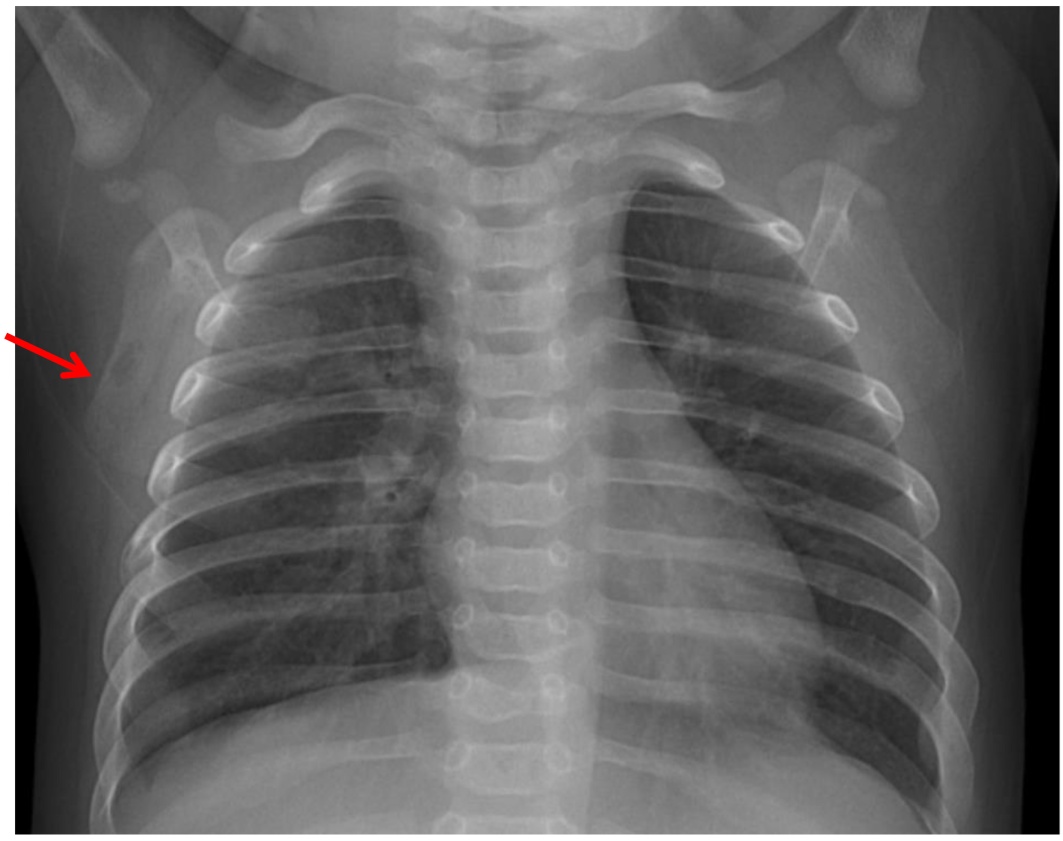

(4) 辅助检查:2025-09-07胸部X线:考虑双肺少许炎症;2025-09-08尿培养:铜绿假单胞菌,头孢他啶2S;2025-09-09血常规 + CRP复查:C反应蛋白30.88 (mg/L)↑,白细胞计数7.63 (×10^9/L) ,中性粒细胞百分率35.10↓,淋巴细胞百分比52.30%↑,淋巴细胞绝对值3.99 (×10^9/L)↑,血红蛋白88 (g/L)↓,血小板计数407 (×10^9/L)↑,血沉49.00↑,白介素644.55 pg/mL:2025-09-09免疫全套:免疫球蛋白IgG 3.48 g/L↓,免疫球蛋白IgGM 0.50 g/L,免疫球蛋白IgA 0.05 g/L↓,补体C3 1.69 g/L↑,补体C4 0.33 g/L;碱性磷酸酶:305.3U/L↑;2025-09-09左侧髋关节及左侧膝关节彩超:未见明显异常;2025-09-09胫腓骨正侧位X线(如图1):左腓骨形态略膨隆,髓腔内见长节段低密度区,边界不清,骨皮质膨胀、变薄,层状骨膜反应,邻近软组织肿胀。

Figure 3. Chest PA X-ray

3. 胸部正位片

右肩胛骨重叠区可见类圆形低密度影,大小约为4 mm × 7 mm。